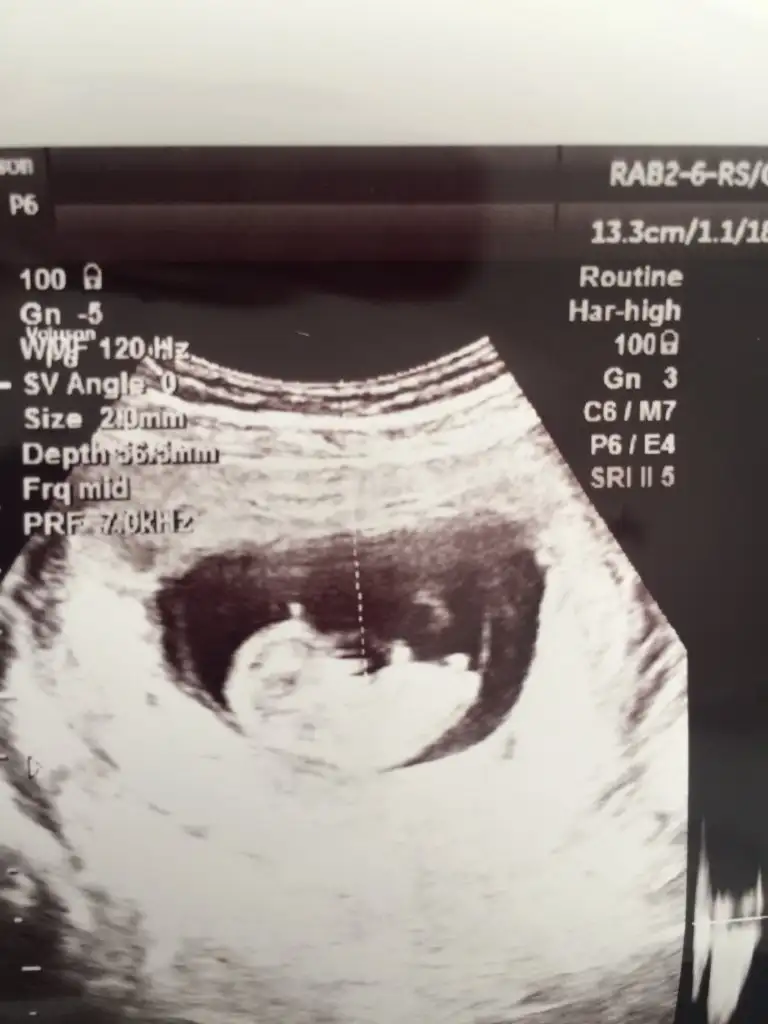

ben bugün doktora gittim geçen haftaki çıkıntıyı göremiyorum dedi.. erkek diye değerlendiriyorum demişti geçen hafta ama şimdi de karışabilir bu haftalarda anlaşılmaz falan dedi..

şaşkınlık içindeyim..

madem karışır ne diye tahmin edip fikir beyan edersin.

bu hafta usg vermedi..

geçen haftaki usg ler.. 11+2